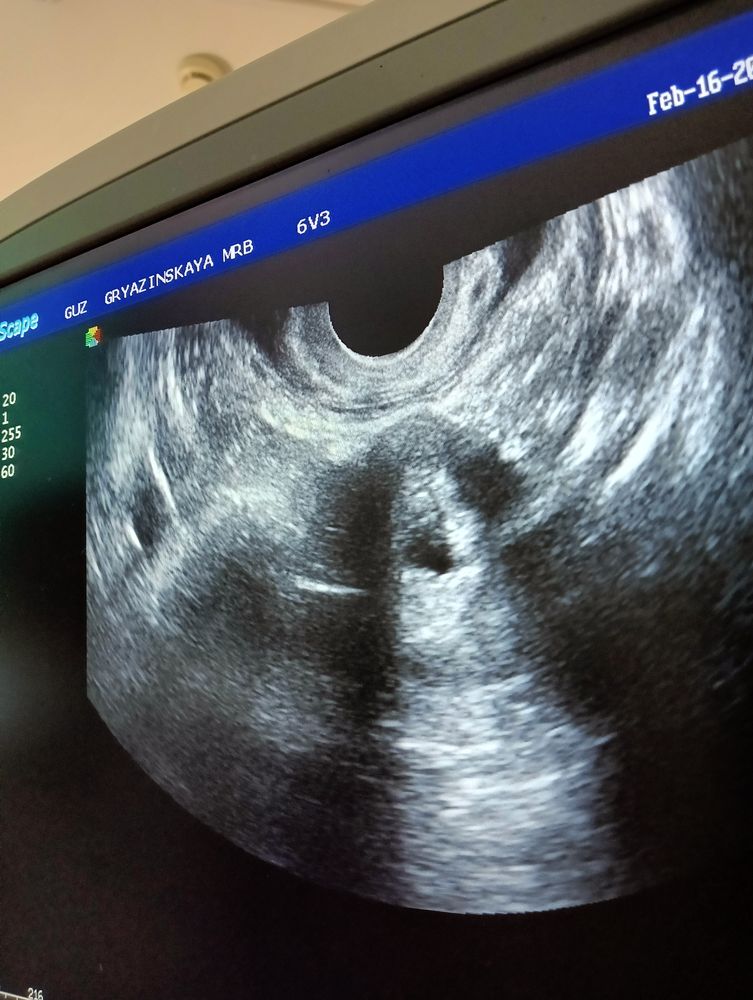

Фотки узи, от которых только грустно. И да, аппарат у нас хрень. Фото ночью не делала. Но там хоть было чётко все. 😐 Шейка матки сказали закрыта.

По моему, нормальные фотки. ПЯ видно, формы оно может быть любой, это не важно. Там даже ЖМ виднеется! Все по сроку.

Светлана, 1-2 и последняя фото - там все видно. А то что кровь мешает диагностике и под некоторыми углами не видно - ну да, так бывает, все маленькое. Аппарат плохой. Это нормально.